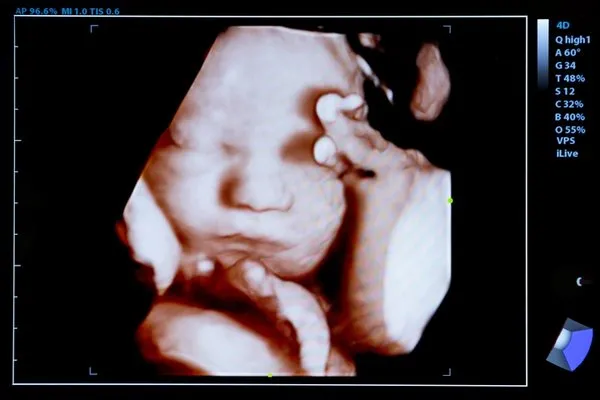

çünkü ultrasonda genellikle down sendromlu bebekler normal görülmektedir. Down sendromlu bebek anne karnında nasıl anlaşılır. Ultrason sayesinde down sendromlu bebeklerin tespit edilme oranı ise 30 dur. Gebelik haftaları arasında bebeğin ense kalınlığının artmasına bağlı da down sendromu.

Down sendromu hakkında ayrıntılı bilgiye buraya tıklayarak ulaşabilirsiniz. 12 haziran 2019 hamilelikte testler kategorisinde e blgn. Doğru cevap ise ultrasonda down sendromu bulgularının olabileceğidir. Hamilelikte ultrason ile down sendromlu olduğu belli oluyor mu.